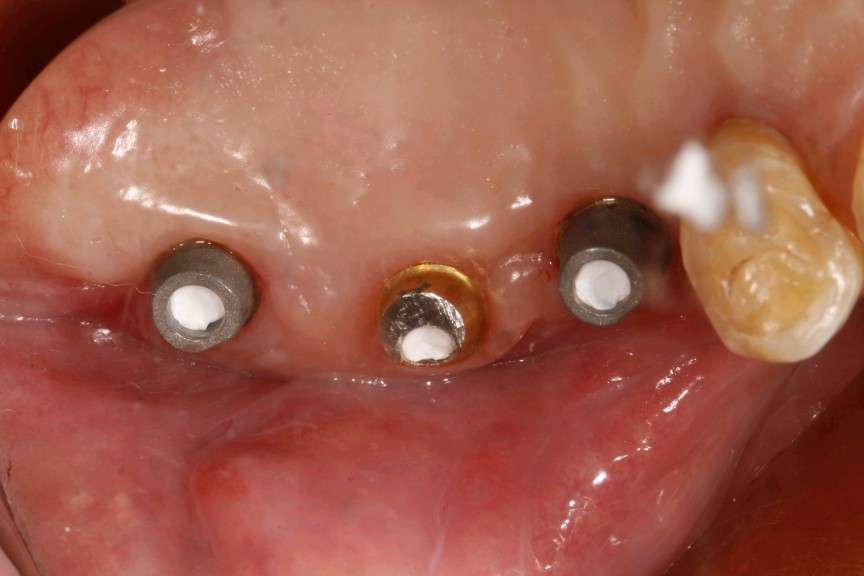

患者男,五十岁,右上后牙缺失一年。治疗计划拔出后种植修复。综合考虑患者自愿选择欧美hiossen种植体。最终15植入hiossen种植体4.5*11.5mm;16、17植入hiossen种植体5.0*10mm。二期三期如期进行。余近日戴牙。